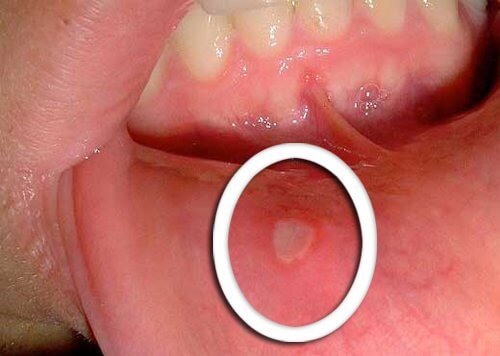

Cambiamenti fisici nella bocca

- Il primo sintomo del tumore orofaringeo è la comparsa di piaghe che non guariscono.

- È comune anche la presenza di macchie rosse o bianche sulla zona della lingua, sulle gengive o agli angoli della bocca.

- È importante essere consapevoli del fatto che bisogna consultare il medico se questi cambiamenti non dovessero migliorare con il passare dei giorni.